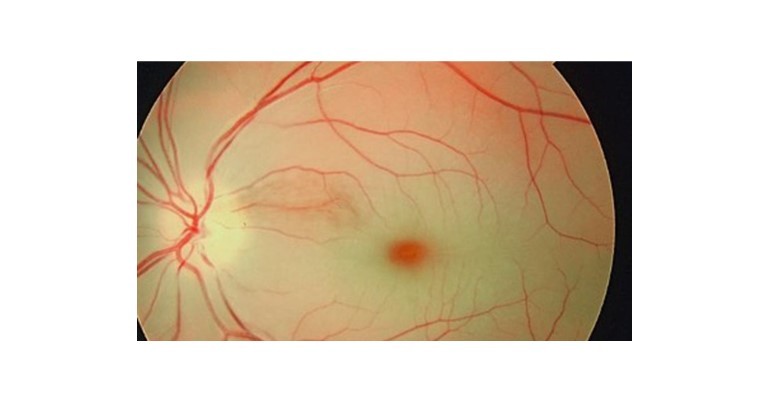

1. Central Retinal artery occlusion: It is characterised by retinal whitening with a macular cherry-red spot. In the case of a branch retinal artery occlusion. A difference between the retina's afflicted and spared portions is made in the event of a branch retinal artery obstruction between affected and spared areas of the retina.

4. Central serous retinopathy: Due to macular subretinal fluid, central serous retinopathy manifests as an abrupt, painless vision loss.